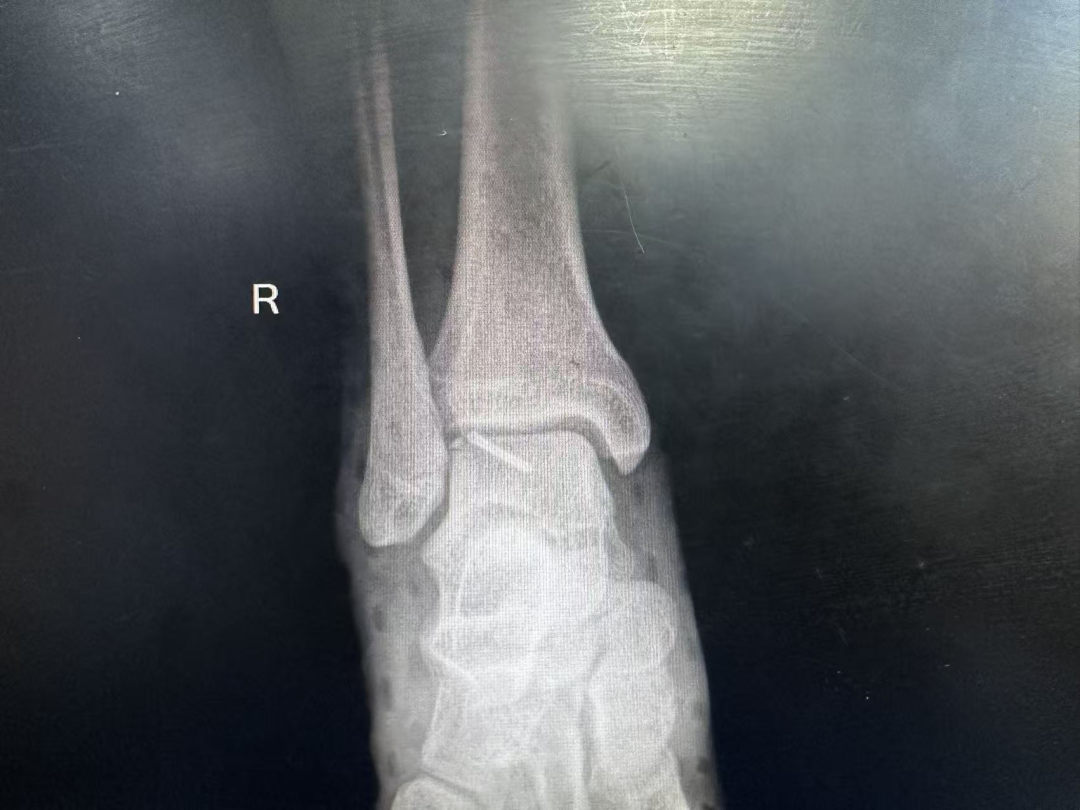

踝关节正位片

术后影像学检查